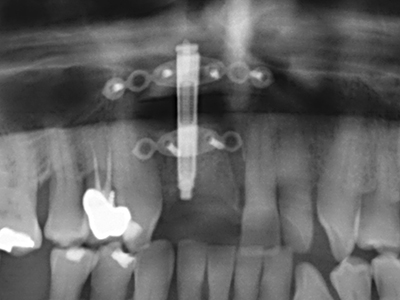

Die Präparation des lateralen Fensters bei der externen Sinusbodenelevation stellt gerade für chirurgisch unerfahrene Implantologen eine große Herausforderung dar. Die knöcherne Bedeckung der Kieferhöhle ohne eine Verletzung der darunterliegenden Schneider’schen Membran abzutragen ist dabei nur ein Teil der Operation – nach Schaffung eines ausreichenden Zugangs muss die Kieferhöhlenschleimhaut vorsichtig mobilisiert werden, um Raum für das einzubringende Material bzw. die Implantate zu schaffen. In dieser Indikation ist die Piezochirurgie zweierlei hilfreich: zum einen kann durch Verwendung diamantierter Instrumente eine selektive Knochenabtragung erfolgen und die darunter liegende Schleimhaut bleibt bei vorsichtiger Vorgehensweise intakt. Zum anderen unterstützen die Ultraschallfrequenzen zusätzlich eine komplikationslose Ablösung der Schleimhaut – sie werden durch spezielle stumpfe Ansätze in den Spaltraum zwischen Schleimhaut und Kieferhöhlenboden übertragen (Cassetta, Ricci et al. 2012, Pereira, Gealh et al. 2014) (Rickert, Vissink et al. 2013). So erscheint es nicht verwunderlich, dass in aktuellen Übersichtsarbeiten über die externe Sinusbodenelevation neben der Verwendung von rauen Implantatoberflächen und dem Einsatz von Knochenersatzmaterialien auch der Einsatz von piezoelektronischen Geräten als positiv bewertet wird (Wallace, Tarnow et al. 2012).

Sollen chirurgische Eingriffe mit unmittelbarer Knochenbeziehung an empfindlichen Strukturen wie Blutgefäßen oder Nerven erfolgen, so bergen rotierende Instrumente ein erhebliches Potential an iatrogener Schädigung. Gerade bei Nervdarstellungen nach iatrogener Schädigung, oder aber im Zuge einer Nervlateralisation für resektive und rekonstruktive Eingriffe oder Implantatinsertionen können piezoelektronische Geräte hilfreich sein Knochendeckel zu präparieren und nervnahe Hartgewebsanteile zu entfernen (Abb. 17-20). Ein leichter Kontakt des Nervstrangs zur Piezospitze bleibt dabei in der Regel folgenlos – allerdings kann eine unvorsichtige Vorgehensweise mit sägeartigen Bewegungen bzw. Ansätzen bei noch vorhandener knöcherner Unterlage durchaus temporäre oder aber auch permanente Nervschädigungen verursachen. Das Risiko einer solchen Schädigung wird jedoch als wesentliche geringer eingeschätzt als unter Anwendung von Säge- oder Fräsinstrumenten (Pereira, Gealh et al. 2014).